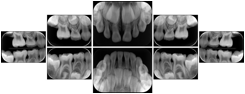

- OO-1. Intra-oral Full Mouth Series Structured Display